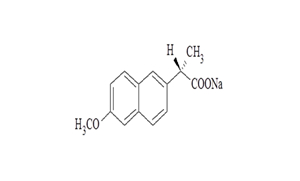

Naproxen Tablets USP

| 250 mg | Tablet | Rx | Naprosyn |  | 62207-745-43 62207-745-47 62207-745-49 |

Medication Guide |

| 375 mg | Tablet | Rx | Naprosyn |  | 62207-746-43 62207-746-47 62207-746-49 |

Medication Guide |

| 500 mg | Tablet | Rx | Naprosyn |  | 62207-747-43 62207-747-47 62207-747-49 |

Medication Guide |